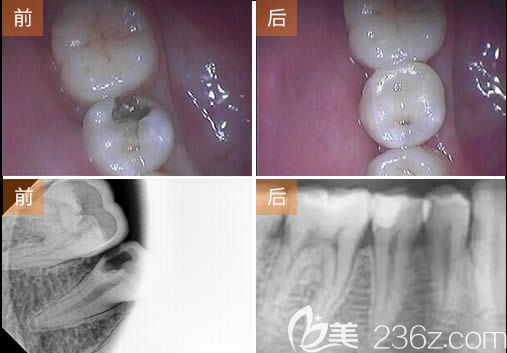

張婉瑜醫(yī)生根管治療牙髓病案例展示:

顧客:劉先生,27歲;

牙齒問題:牙齒齲壞、牙髓炎;

治療方案:根管治療術(shù)+樹脂補(bǔ)牙;